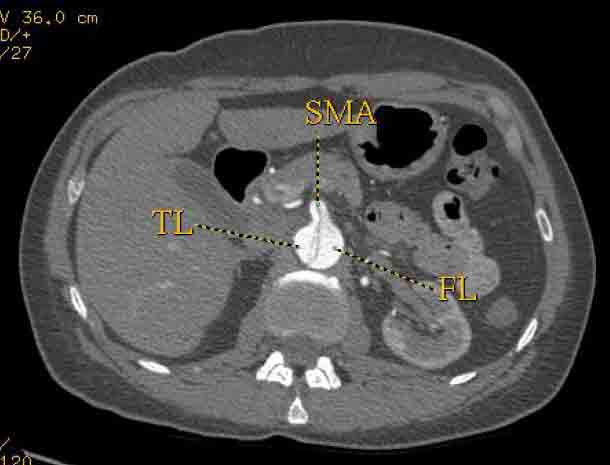

The patient was taken to the hybrid operating suite and a thoracic aortogram was performed. The aortogram confirmed the chronic Type B aortic dissection with a patent false lumen and a fenestration just beyond the left subclavian artery. An intravascular ultrasound (IVUS) was also performed of the entire aortic arch and descending thoracic and abdominal aorta. The IVUS also confirmed that there was an adequate proximal landing zone beyond the left subclavian artery consisting of normal aorta where we would be able to achieve adequate seal of the endovascular stent graft. The septal fenestration began approximately 1.5 cm distal to the left subclavian artery. The true lumen was compressed distally. (Figure 2) The celiac artery appeared to come off the true lumen. (Figure 3) The dissection extended into the superior mesenteric artery and the artery was perfused from both the true and false lumen. (Figure 4) The left renal artery came off the false lumen. (Figure 5) The right renal artery came off the true lumen.